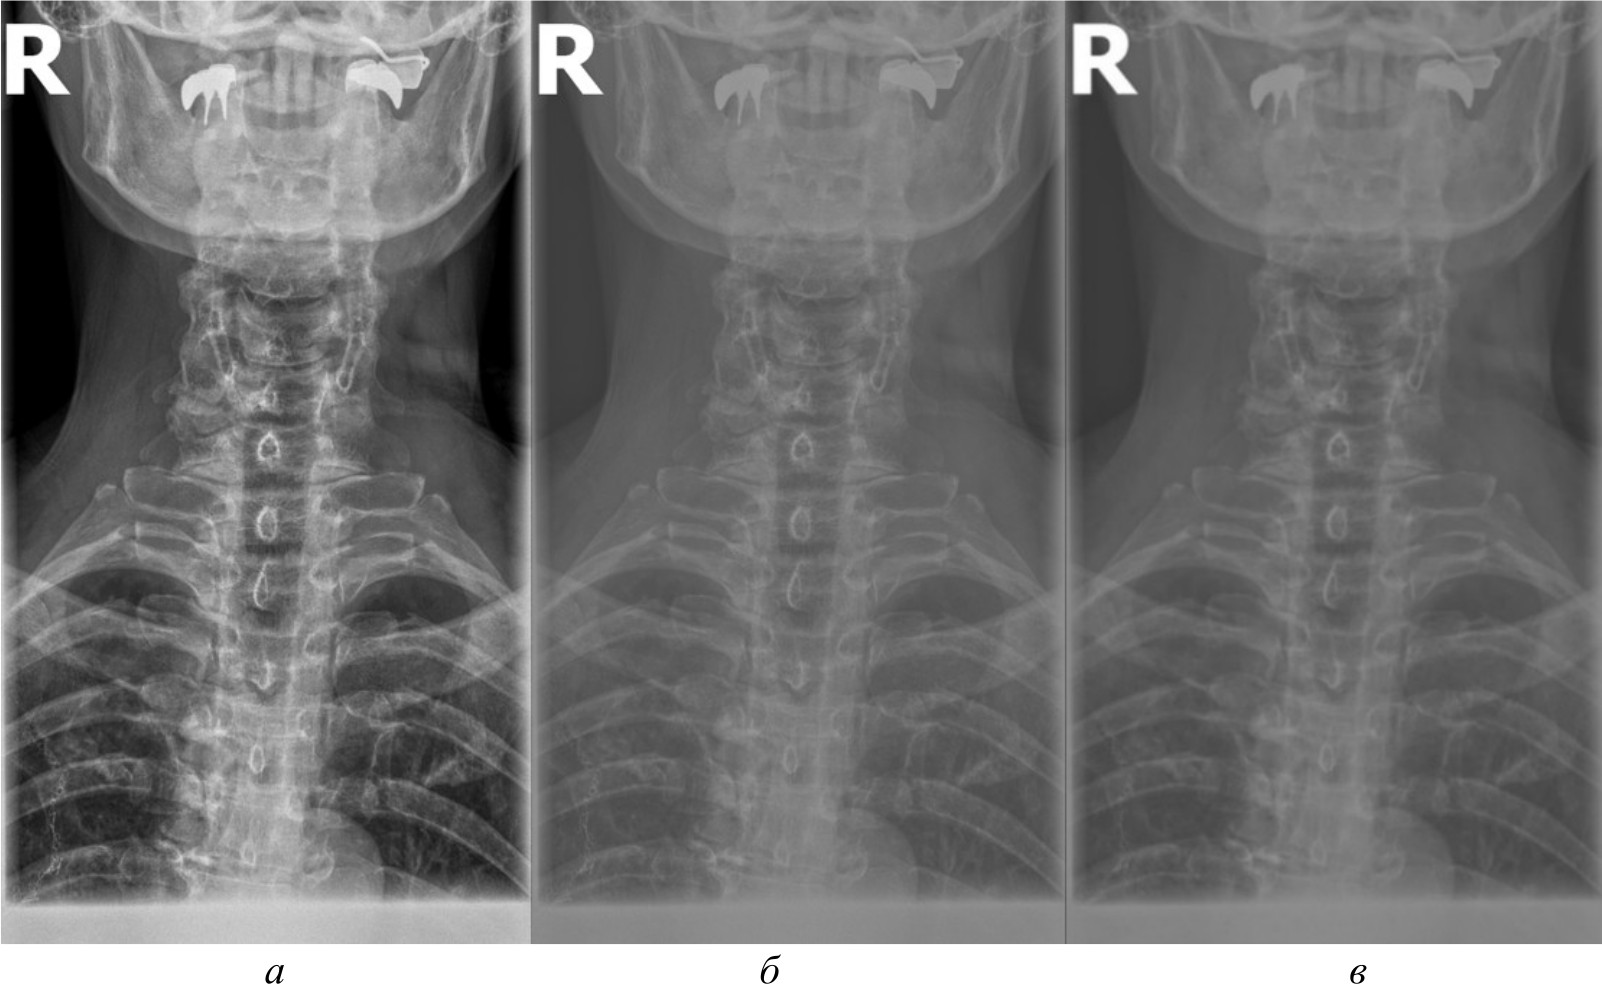

Для сравнительного анализа использовались различные методы и алгоритмы компьютерного зрения. Помимо изображений в формате PNG, конвертированных из исходных DICOM-файлов, применялись и другие подходы, направленные на извлечение более качественных изображений непосредственно из DICOM-данных, среди которых:

- базовое отображение Python. Изображения загружены в Python и отображены при помощи библиотеки Pillow без применения каких-либо дополнительных преобразований. Данный метод представлен на рис. 2, б;

- медианный фильтр. Для сглаживания шумов и артефактов на изображениях к базовому отображению Python применен медианный фильтр из библиотеки OpenCV. Размер окна фильтра был подобран эмпирически. Данный метод обработки представлен на рис. 2, в;

- адаптивная эквализация гистограммы. Для улучшения локального контраста изображений помимо базового отображения Python использована адаптивная эквализация гистограммы из библиотеки OpenCV. Метод адаптивной эквализации представлен на рис. 3, a;

- стандартная эквализация гистограммы. Для сравнения с адаптивной эквализацией помимо базового отображения Python применена стандартная эквализация гистограммы из OpenCV. Данный метод представлен на рис. 3, б;

- гамма-коррекция. Для регулирования яркости и контрастности изображений, а также для сравнения с двумя предыдущими эквализациями использована гамма-коррекция. Значение гамма-параметра подбиралось эмпирически. Гамма-коррекция представлена на рис. 3, в.

Рис. 2. Изображение, полученное при помощи специализированного программного обеспечения (а), метод базового отображения в Python (б), метод базового отображения Python с применением медианного фильтра (в)

Исходя из полученных изображений при использовании различных методов можно сделать следующие выводы:

- базовое отображение DICOM-данных с помощью библиотеки Pillow показало наличие значительного количества шумов и размытых объектов на полученных изображениях, что затрудняет четкое обнаружение анатомических ориентиров;

- применение медианного фильтра для сглаживания артефактов привело к чрезмерному размытию деталей на изображениях, сделав их еще менее пригодными для дальнейшего анализа;

- использование методов эквализации гистограммы продемонстрировало значительное улучшение контрастности и четкости визуализации анатомических структур по сравнению с базовым отображением и медианной фильтрацией;

- гамма-коррекция изображений, в отличие от эквализации, больше повлияла на яркость, нежели на контрастность, поэтому показала себя хуже в контексте задачи выделения ключевых анатомических ориентиров;

- отображение изображений в формате PNG, полученных из исходных DICOM-данных после применения ряда предварительных обработок с помощью специализированного программного обеспечения, продемонстрировало качество визуализации несколько меньшее, чем у методов эквализации, но при этом превосходящее качество других рассматриваемых методов обработки. В итоге комплекс предварительных обработок, необходимых для конвертации DICOM-данных в формат PNG, позволяет достичь качества визуализации, которое хотя и уступает эквализации, но превосходит другие методы.

Рис. 3. Метод адаптивной эквализации гистограммы, метод стандартной эквализации гистограммы, метод гамма-коррекции